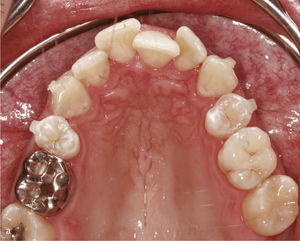

El paciente se presentó en nuestro centro con el siguiente cuadro: dentición permanente con proinclinación de dientes anteriores y desviación de la línea media, diente 53 persistente, dientes 13 y 23 elevados y desplazados hacia vestibular, curva de Spee marcada con extrusión del sector anteroinferior, dientes rotados y apiñados en maxilar y mandíbula, clase II de Angle con un resalte de 4mm y sobremordida de 0mm, además de ausencia de guía canina (figs. 13a a 13c y 14a a 14e).

El plan de tratamiento incluyó el establecimiento de una clase I de Angle con sobremordida horizontal y vertical fisiológicas mediante la distalización del sector posterosuperior, con corrección de los caninos superiores y aseguramiento de una guía canina. Las arcadas se dotaron además de una apariencia armoniosa eliminando la giroversión y los apiñamientos mediante la reducción del esmalte interproximal y el ajuste de las líneas medias. El paciente optó por un tratamiento con el sistema Invisalign alternativo a la aparatología fija con brackets. Se colocó un atache rectangular vertical en los dientes 13 y 23 y, en el curso del tratamiento, también en los dientes anterosuperiores y en el diente 43. Además durante todo el tratamiento el paciente llevó elásticos de clase II en ambos lados, del diente 14 al diente 46 y del diente 24 al diente 36 para obtener el anclaje necesario durante la distalización. La figura 15 muestra la situación intraoral de un caso similar con brackets en los dientes 13 y 46. En la zona de los brackets se acortó el alineador. Además de los alineadores se utilizaron elásticos de clase II del diente 13 al diente 46.